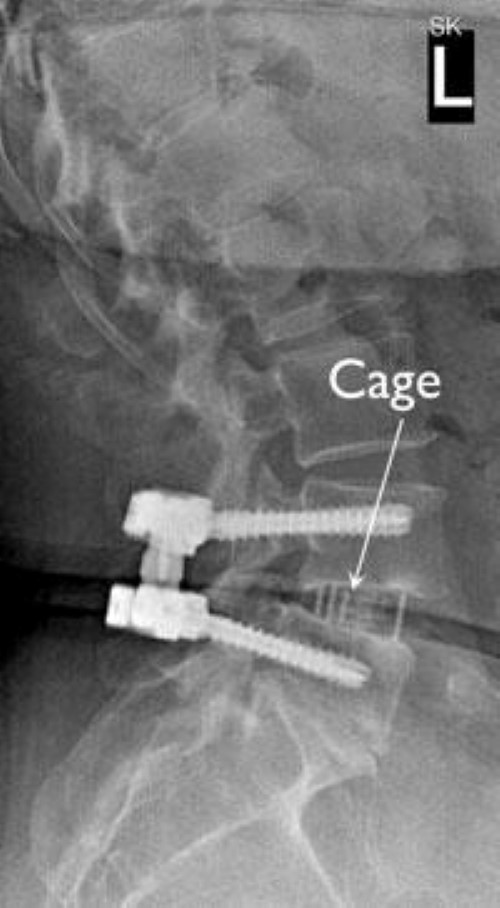

Sideview (lateral) Color XRay of a Lumbar Fusion with Annotations How Soon Can You Bend After Spinal Fusion Light chores around the home; Spinal fusion is a common form of back surgery used to treat several kinds of. A doctor may recommend gentle walking and carrying out basic daily living. How long after back surgery can you bend over? By 4 to 6 weeks after lumbar fusion surgery, most patients are cleared to return to school or work. How Soon Can You Bend After Spinal Fusion.